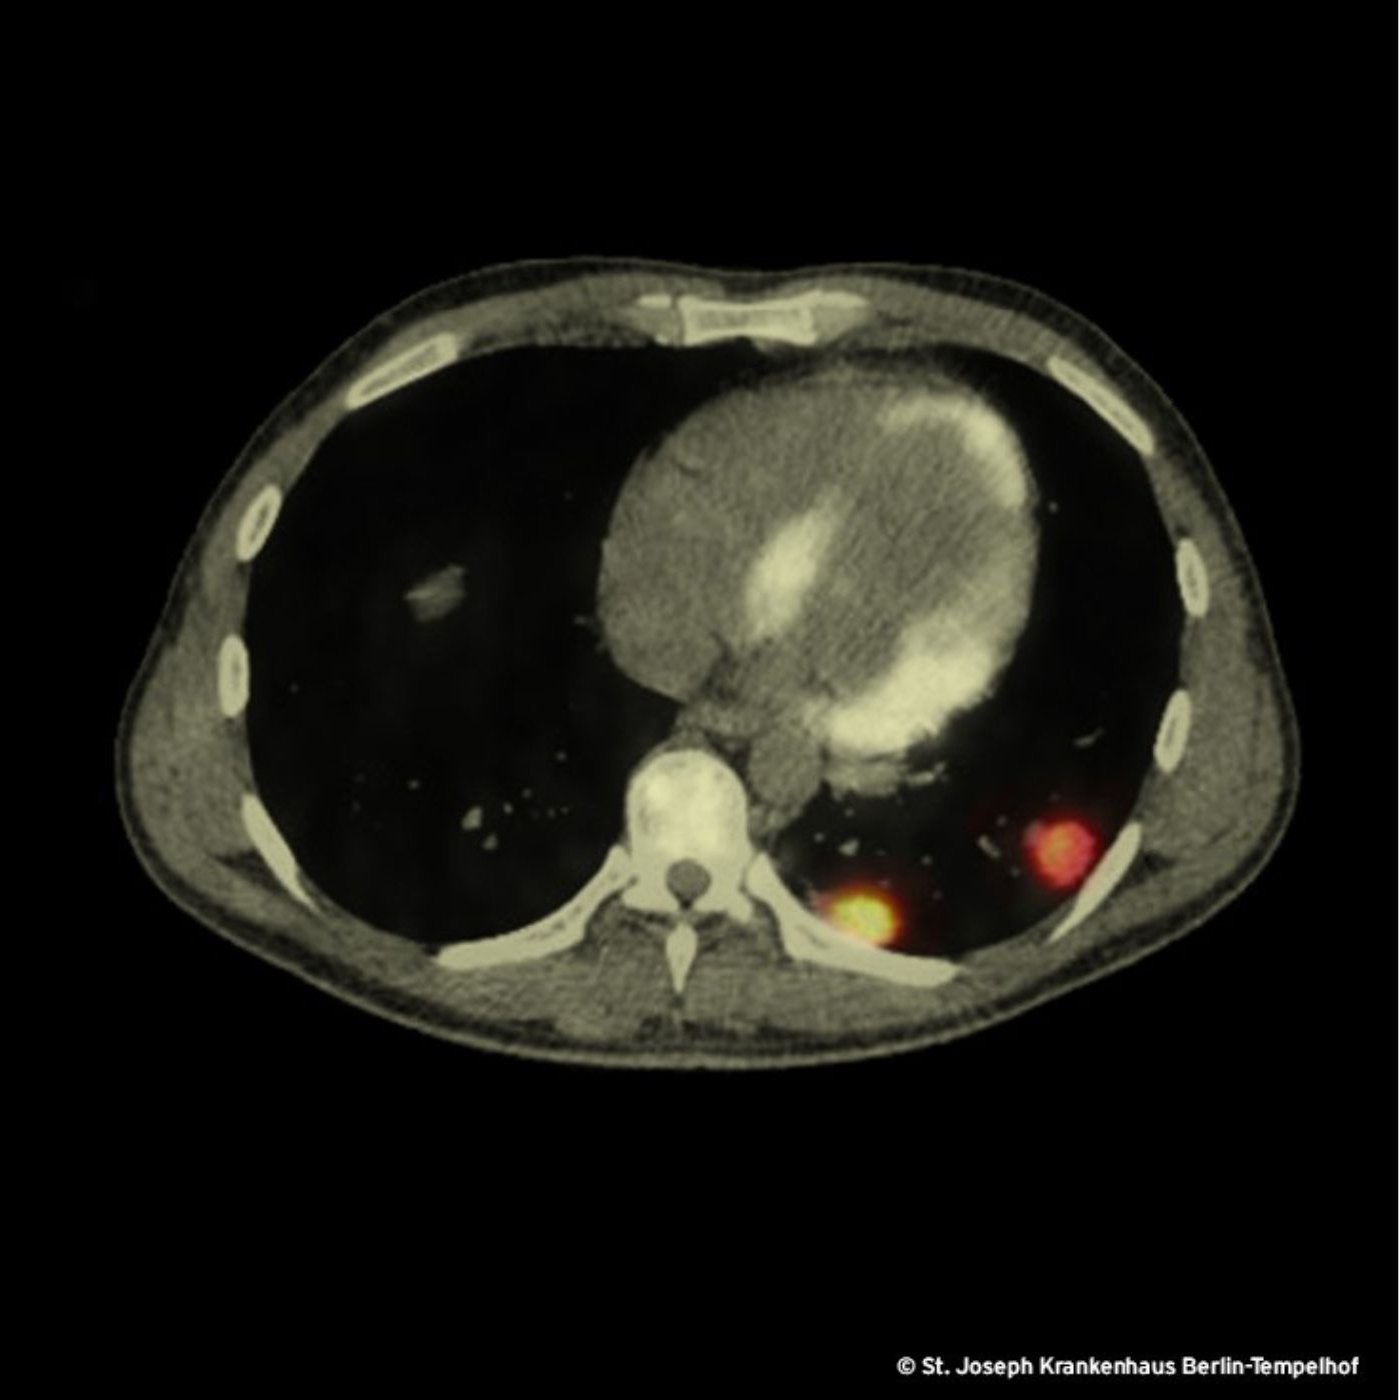

Der Verdacht auf eine maligne Erkrankung treibt uns zu einem PET-CT, welches 3 Wochen nach der Erstvorstellung eine schockierende Größenprogredienz der pulmonalen und vertebralen Läsionen enthüllt. Der Radiologe fällt das Urteil: bösartige hämatologische Systemerkrankung. Das Bild zeigt zwei der fünf pulmonalen Herde, die im PET-CT hohe Stoffwechselaktivität aufweisen.